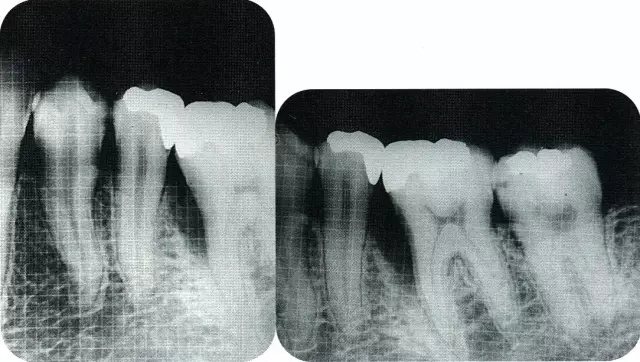

640.webp (1).jpg

▲圖7-2  術(shù)前x片。確認存在垂直性深骨缺損。